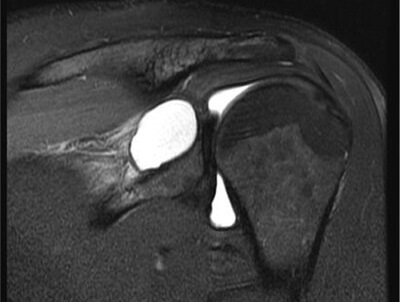

Your doctor may also send you for imaging tests, usually an ultrasound or MRI scan to assess the shoulder further. This helps to identify the type of cyst and any underlying causes that may have caused it to form e.g. labrum tear or rotator cuff damage.